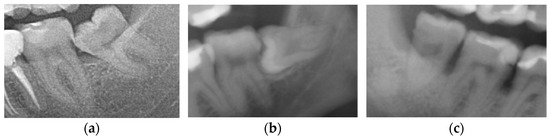

M3s were divided, according to the eruption status into (1) non-impacted (N-M3), when the tooth reached the occlusal plane, (2) completely impacted (I-M3), when the tooth was completely surrounded by bone, and (3) partially impacted M3, when the crown of a tooth was situated above the bone edge, but had not reached the occlusal plane (Figure 2) [2].

Figure 2. Third molars depending on the eruption status: (a) non-impacted (erupted) M3, (b) partially impacted M3, and (c) completely impacted M3.